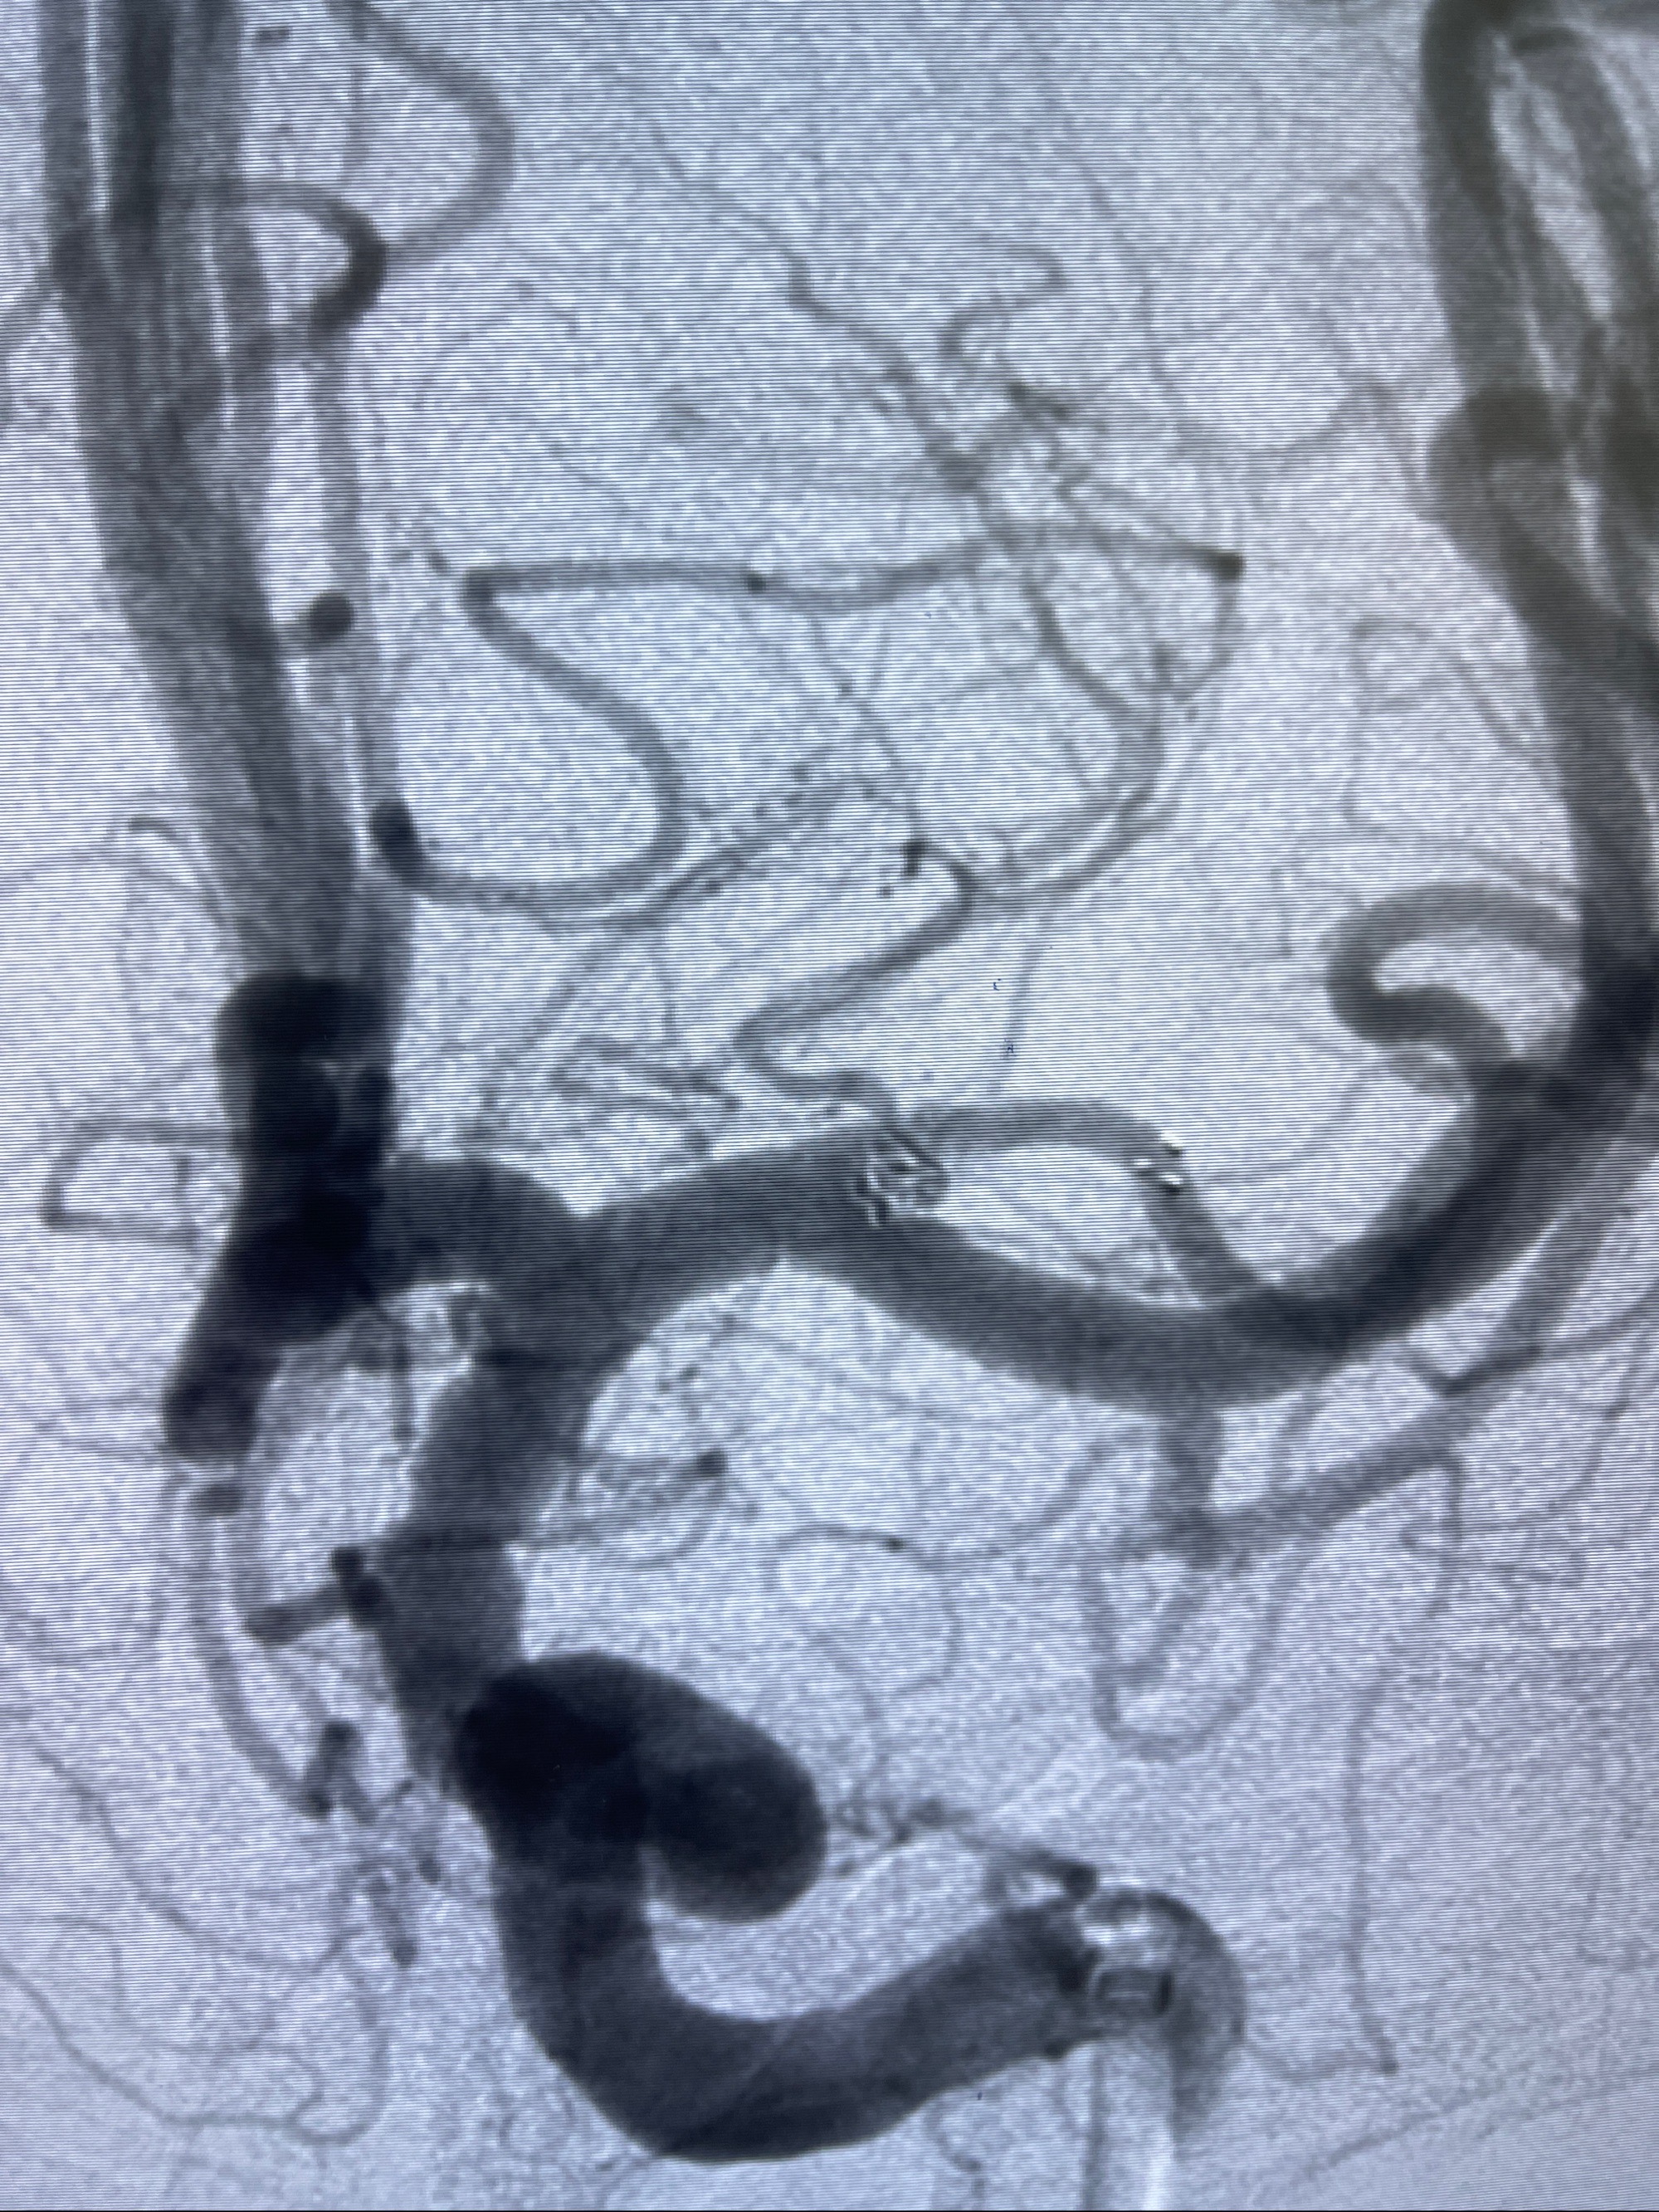

术后即刻CT